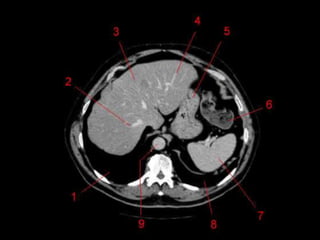

• Os oito segmentos são divididos:

– A primeira divisão é realizada dividindo através da

Porta Hepática, em esquerdo (I a IV) e direito (V a VIII)

– A divisão é feita baseada em um relógio

– Caudado é o segmento I

– No ‘lobo’ esquerdo, o IV separa-se do II e do III pela

veia hepática esquerda, representado

anatomicamente pelo ligamento falciforme.

– II e III se dividem através de uma linha imaginária

transversal na altura da porta hepática.

– No ‘lobo’ direito, se divide os segmentos através de

uma linha transversal e pela veia hepática direita.

Subdivisão Funcional • Osoito segmentos são divididos: – A primeira divisão é realizada dividindo através da Porta Hepática, em esquerdo (I a IV) e direito (V a VIII) – A divisão é feita baseada em um relógio – Caudado é o segmento I – No ‘lobo’ esquerdo, o IV separa-se do II e do III pela veia hepática esquerda, representado anatomicamente pelo ligamento falciforme. – II e III se dividem através de uma linha imaginária transversal na altura da porta hepática. – No ‘lobo’ direito, se divide os segmentos através de uma linha transversal e pela veia hepática direita.